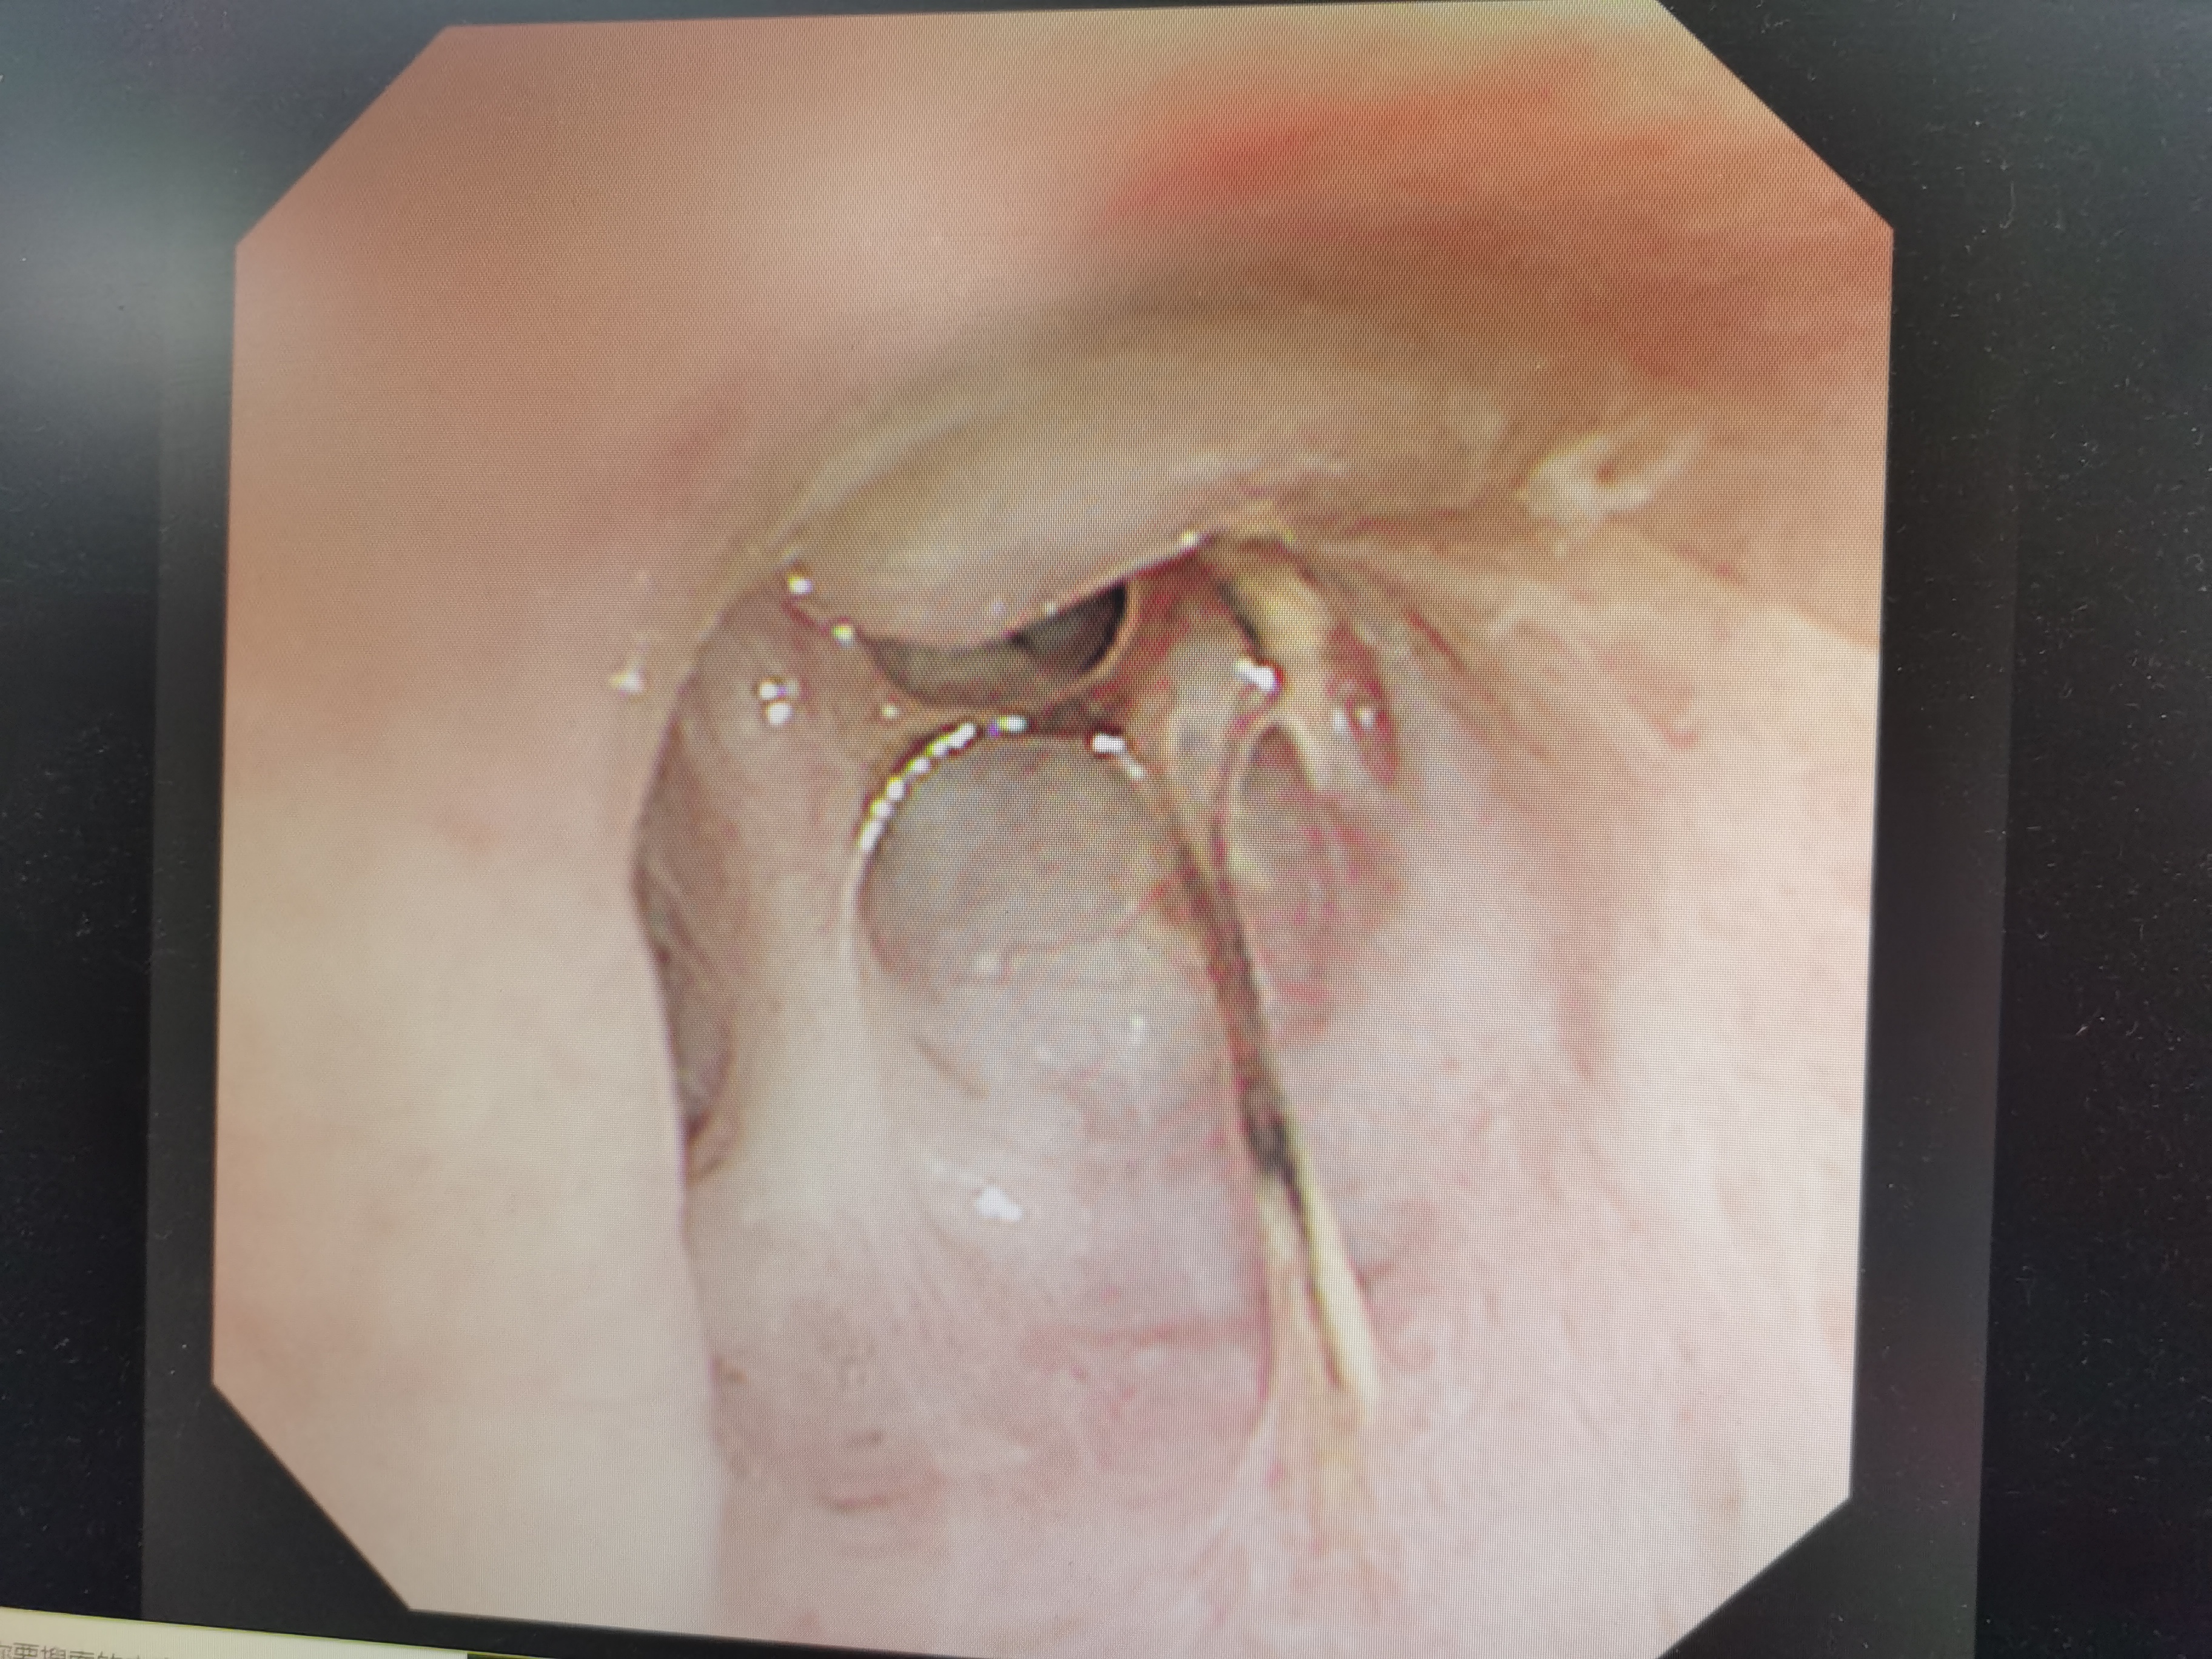

然而,凭借多年胸腔镜技术的沉淀、积累,毁损肺很快就被切除。之后,主刀医生蒋钰辉副主任,又对曾经生长肺鳞癌的右上支气管病灶进行切除。按照肺癌手术原则,他们先以支气管上原肿瘤病灶处为中心,在其上下两个方向,选择适度安全距离,进行上下两端的切除,剔除病灶。然后将两处断面取样,进行快速病理分析,确定断面已经远离肺癌病灶,没有癌细胞抵达此处。之后,像「缝衣袖」一样,将剩余的支气管上下连接。